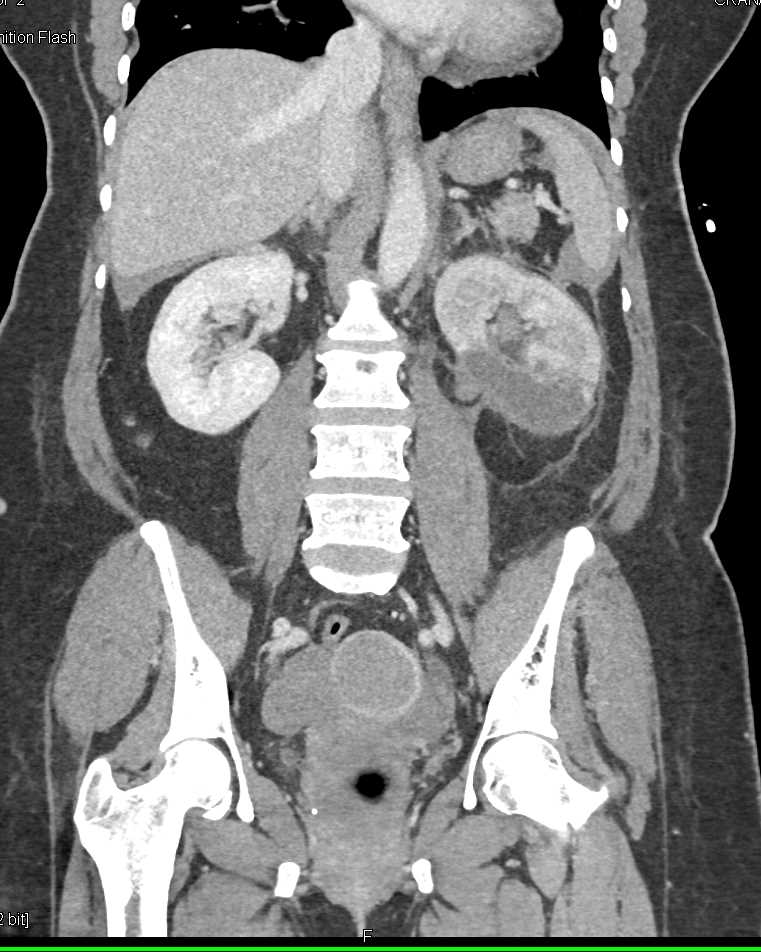

Acute Pyelonephritis Right Kidney